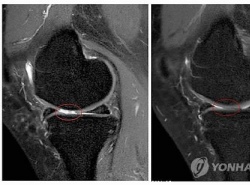

"ÀÚ°¡Áö¹æ¼¼Æ÷ À̽Ä, ÅðÇ༺°üÀý¿°¿¡ È¿°ú"

"ÀÚ°¡Áö¹æ¼¼Æ÷ À̽Ä, ÅðÇ༺°üÀý¿°¿¡ È¿°ú" (¼¿ï=¿¬ÇÕ´º½º) ÇѼº°£ ±âÀÚ = ÀÚ½ÅÀÇ Áö¹æÁ¶Á÷¿¡¼ äÃëÇÑ ÀÚ°¡Áö¹æ¼¼Æ÷ À̽ÄÀÌ ÅðÇ༺ °üÀý¿° Ä¡·á¿¡ È¿°ú°¡ ÀÖ´Ù´Â ¿¬±¸°á°ú°¡ ³ª¿Ô´Ù. ¼¼Æ÷Ä¡·á¡¤¸é¿ª¿ä¹ý ...